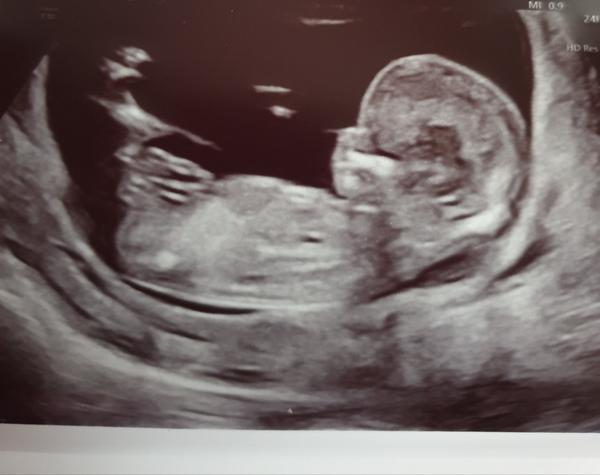

poznal byste pohlaví miminka?

Fotky jsou ze screeningu v trimestru a stáří miminka je 13+0.